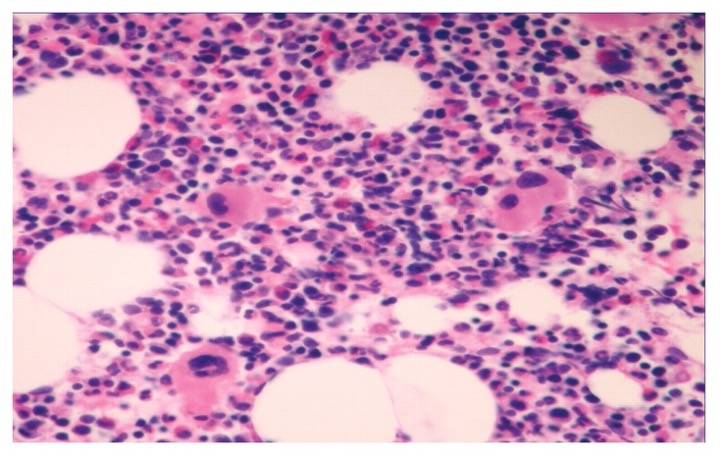

Investigations (additional)

Haematology